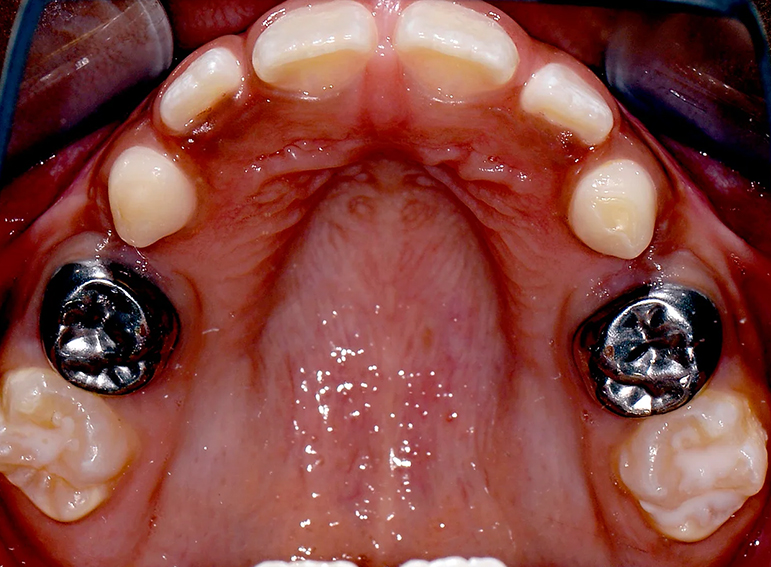

Hypoplastic primary molars: Placement of hall crowns, extraction of URD and ULD, composite restorations of LRD, LLD and C’s and fissure sealants of adult molars.